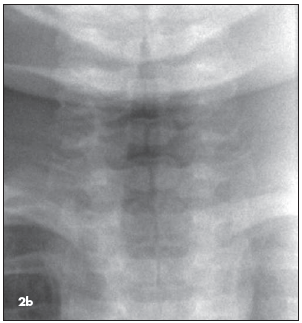

Croup. Because it is summer, croup is unlikely. In any event, the long, smooth, steeple-like narrowing of the subglottic airway that is characteristic of croup is not evident. (Figure 2b shows signs of croup in a different patient.)